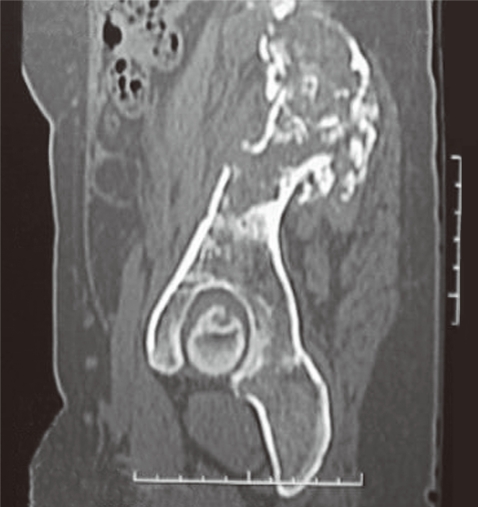

The patient continued with the pelvic pain although postoperative MRI showed reduction in size of the lesion along the right iliac bone and sacroiliac joint. No new lesion was, however, seen. The x-ray of the pelvis and hips revealed cortical irregularity with ill defined lytic defects and linear areas of patchy sclerosis along the right iliac blade (

Fig. 1). She continued with pain and follow-up CT reviewed after 8 months revealed extension of the disease. The patient was then referred to our hospital. On physical examination, local tenderness was present on the back of the right limb and hip. The range of motion of the right hip was painful and restricted. No distal neurovascular deficits were present. Blood investigations were within normal range. Surgery was planned for removal of the residual disease. The preoperative MRI and CT showed progression of the disease. The CT showed a multiloculated cystic lesion (

Fig. 1X-ray of pelvis and hips revealed ill-defined lytic defects and linear areas of patchy sclerosis along the right iliac blade (arrows).